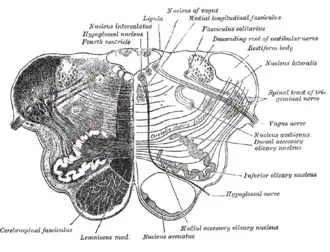

Transverse section of medulla oblongata below the middle of the olive.

Transverse section of medulla oblongata below the middle of the olive. -